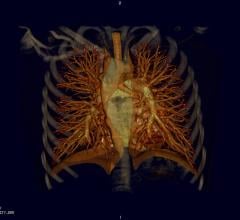

March 19, 2015 — Use of computed tomography coronary angiography (CTA), which provides 3-D images of the heart, coupled…

March 16, 2015 — Results from the PROMISE clinical trial confirmed what many cardiologists and radiologists have long…